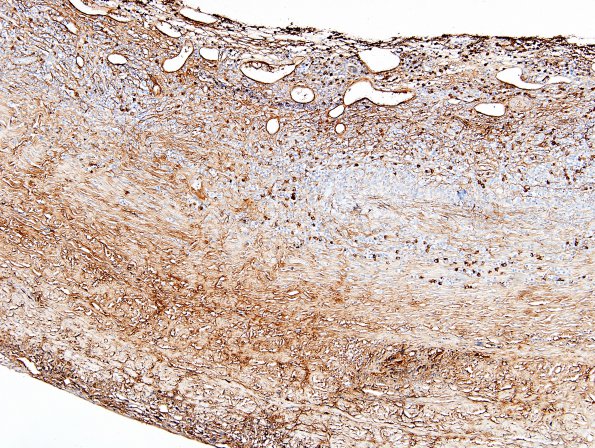

1F1-3 This series of images represent the staining pattern of IgG4 in the same areas as IgG (#1E1-3). Counts of IgG4 immunoreactive cells ranged from 20-60/HPF (IgG4 IHC). In some areas IgG4 immunoreactivity demonstrated numerous IgG4-positive plasma cells, comprising approximately 40% of that cell population. The IgG4 to IgG ratio was markedly increased in some sites (>4X). In-situ hybridization for EBER was negative. Molecular PCR studies were negative for clonal rearrangement.